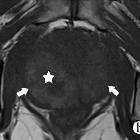

Three morphological MRI patterns have been described which are diffuse, nodular (tumor-like), and cystic with mural nodule .

Signal characteristics include

- T2: affected regions hypointense

- C+ (Gd): no enhancement following Gd-DTPA